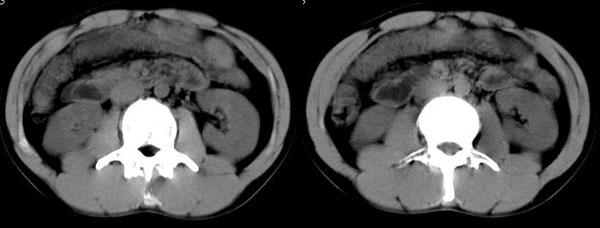

以下是引用晓杰在2006-8-26 21:18:00的发言:[br]肝右叶前段片状低密度灶,边缘模糊。肝内胆管扩张。考虑肝ca? 肝脓肿?[br][br][br]胰头增大,结构模糊,考虑:占位病变。建议增强